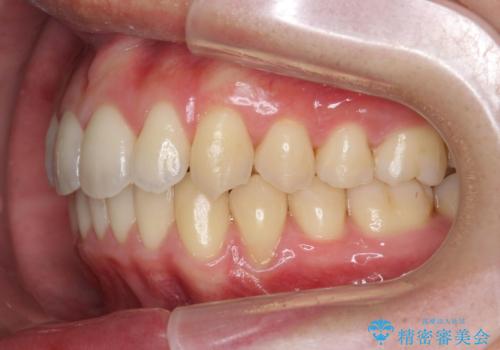

過蓋咬合・上顎前突・叢生を改善するマウスピース矯正

20時間以上のマウスピース装着、ゴムかけを遵守していただいたおかげでしっかりと噛み合わせ、がたつきの改善を行うことができました。